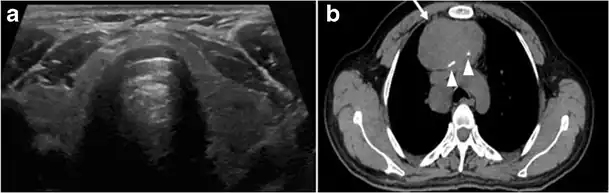

Fig. 7. A 51-year-old female patient post total thyroidectomy for PTC with elevated thyroglobulin measurement. an Axial non-enhanced CT scan of the neck at the level of the thyroid bed demonstrates a well-defined, rounded, homogenously dense soft tissue situated between the trachea and left internal jugular vein (white arrow). b Transverse ultrasound image of the neck demonstrates a well-defined, homogeneous, hypoechoic soft tissue nodule measuring 6 mm (white arrow) with no detected micro-calcifications. Biopsy showed a predominantly residual normal thyroid tissue with micro-foci of PTC.[1]